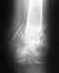

сложный перелом бедра. дайте свою оценку пожалуйста

закрытый полифокальный многооскольчатый перелом средней и нижней трети правой бедренной кости со смещением обломков.

Здравствуйте, травма была получена в дтп 06.09.2012 вытяжка и подготовка до 20.09.2012 далее операция остеосинтез илизарова, потом вторая операция 22.10.2012 фиксация промежуточного отломка на двух уровнях. Скажите пожалуйста, все в порядке? Снимок последнего рентгена от 10.06.2013 приложу. Далее сделаю очередной снимок, потом выложу.http://s019.radikal.ru/i609/1308/32/7e785b467241.jpghttp://s019.radikal.ru/i619/1308/25/5747668cf4ae.jpghttp://s017.radikal.ru/i444/1308/9e/4fdc42e9cd6e.jpg